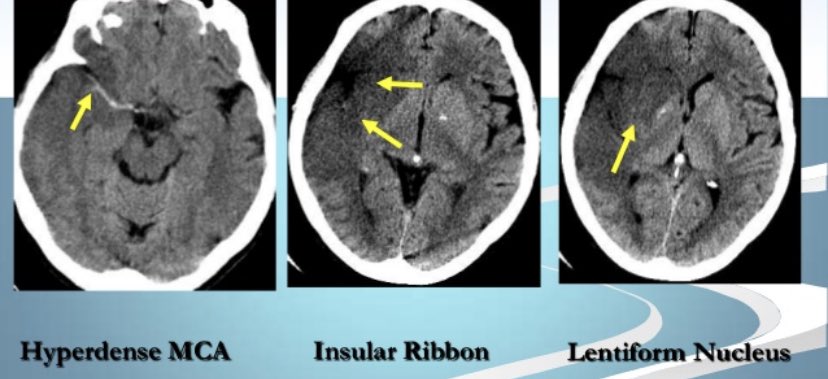

▫️Acute ischemic stroke 🌟🧠

✳️Axial CT of the brain demonstrate that the right MCA is hyperdense and there is loss of normal grey-white matter differentiation in the MCA territory

⏺Remember in the CT, The earliest finding of MCA occlusion is:

✳️hyperdense MCA sign ➡️

seen immediately and represents direct visualization of thrombus

✳️loss of grey-white matter differentiation ➕ hypoattenuation of deep nuclei

✳️cortical hypodensity ➕parenchymal swelling